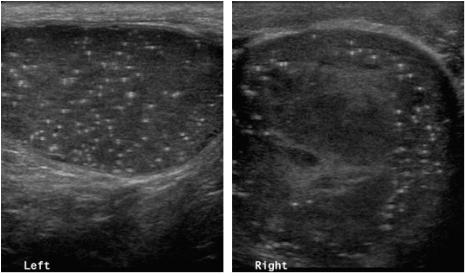

고환 초음파 검사는 고환암의 가장 빠르고 비교적 정확한 검사로서, 고환 내 종물의 유무, 부고환의 병적 소견 및 음낭 수종과의 감별 진단에 도움이 되므로, 고환암이 의심되는 경우 가장 널리 시행되는 검사입니다.

[사진] 초음파에서 좌측에 비하여 우측 고환에 비교적 균질한 내부 음향을 보이는 종물이 관찰됩니다.